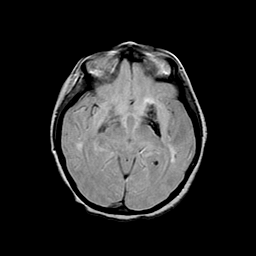

Basal Ganglia Calcification: proton density-weighted MR -- Slice #8

[Home][Help][Clinical] Slice 8